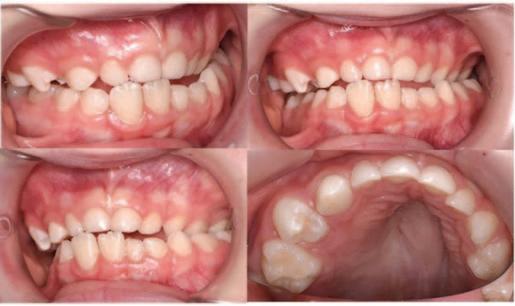

This patient first attended the Oral Surgery Department of Royal School of Dentistry Belfast for removal of a compound odontome in the right mandibular premolar region. This was an incidental finding discovered during assessment for orthodontic treatment (Figure 1). There was no evidence at that time of any other supernumerary teeth elsewhere in the jaws. This compound odontome tooth was surgically removed at that time following the informed consent process. The patient subsequently completed orthodontic treatment. Eight years later, at the age of 21, the patient was referred to the Oral Surgery Department for a second time due to the incidental finding of another supernumerary tooth on the contralateral side (Figure 2). The patient reported no relevant medical or genetic conditions. There was no reported family history

of supernumerary teeth. Clinical examination at age 21 years revealed a wellaligned dentition with a maxillary bonded retainer in place (Figure 2). No symptoms were reported related to the supernumerary teeth. None of the teeth were tender to percussion and all adjacent teeth exhibited a positive response to ethyl chloride. There was a palpable lingual bulge in the alveolar region of the lower left second premolar and first permanent molar. The panoramic radiograph indicated the presence of a radiopaque lesion and a radiolucent lesion in the left mandibular premolar region (Figure 3). A conebeam computed tomography scan was recorded to further characterise the lesion and surrounding area to aid surgical planning (Figure 4).

The patient was happy with the outcome of their previous orthodontic treatment and no further orthodontic treatment was planned. The risks and

benefits of surgical removal of the supernumerary teeth were discussed with the patient, including consideration of the proximity of the roots of adjacent teeth, and the inferior alveolar canal. It was agreed that a further radiographic reassessment would be carried out in 18 months to monitor for the possibility of cystic change or resorption. The possibility of further supernumerary development was discussed with the patient.